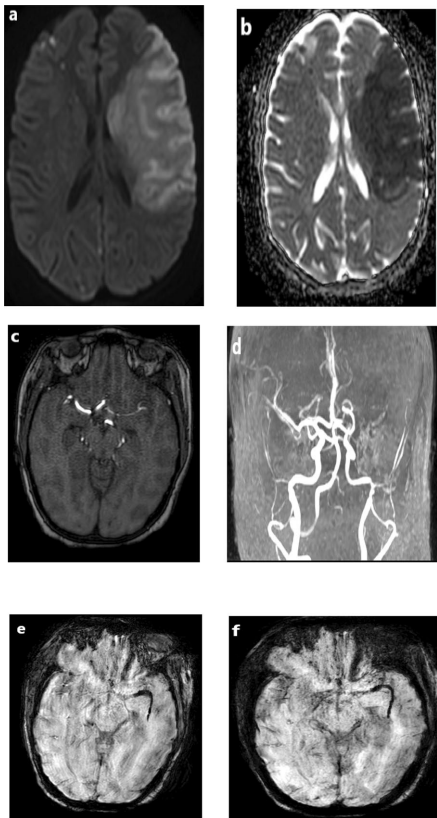

定位一致性:Kappa检验显示两种技术对MCA、ACA、PCA血栓定位具有完美一致性(K=1.0),但对ICA仅达中等一致性(K=0.787)。典型病例中,27岁女性患者左侧MCA全程血栓在SWI清晰显示M1-M3段SVS(图1),而TOF MRA仅显示M1段闭塞。

长度测量:SWI测得血栓长度范围0.4-3cm,47岁女性患者左侧PCA-P1段3cm长血栓(图3)的精确测量为血管内治疗提供关键参数。